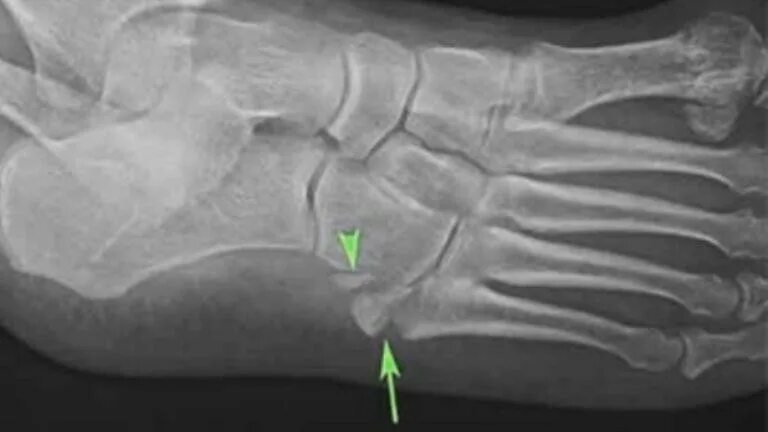

Перелом задней кости стопы